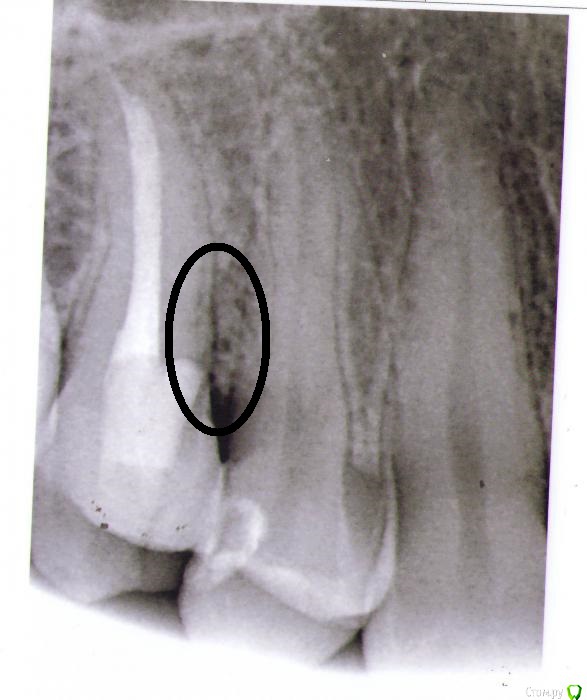

Zub15 Опубликовано 14 мая, 2015 Поделиться Опубликовано 14 мая, 2015 Здравствуйте! Зуб1.5 лечили по глубокому кариесу осенью 2014г. После этого около 3 месяцев не проходили самопроизвольные ноющие боли. В итоге в конце января 2015г. постановили что пульпит таки необратимый и провели эндодонтическое лечение. Через 2 недели появилась боль от горячего. Пока попала к доктору прошло дней 5. За это время ощущения от просто чувства тяжести в первые дни усилились до очень острой, нарастающей первые несколько секунд боли, по продолжительности около 10 минут и в эти моменты причинный зуб реагировал еще и на накусывание. В середине февраля зуб снова вскрыли, искали дополнительные каналы - не нашли, обработалди еще раз тот же канал и оставили кальций под временной пломбой. Первые несколько часов после лечения все было хорошо, зуб не болел. К вечеру появилась ноющая боль, которая постепенно училивалась и к ночи стала нестерпимой. К утру следующего дня боль не прошла, зуб снова вскрыли, заменили кальций и снова под временную пломбу. После все вроде нормализовалось. Через 2 недели когда убрали кальций и запломбировали каналы постоянным материалом снова такая же картина. Первые несколько часов все норм, к ночи разболелся сильно. 4-5 дней эту боль перетерпела и потом постепенно она пошла на спад. В итоге еще недели 2 зуб наблюдали под временной пломбой, боли как таковой не было, но реагировал на постукивание. На сегодняшний день сильной боли нет, на горячее тоже не реагирует, но периодически слабо поднывает где-то в районе 1.4-1.5 чаще по ночам и если в это время пошатать зуб 1,5 - начинает ныть сильнее. Если постучать больно только когда стучишь по передней стенке. И больно чистить нитью между 1.4 и 1.5, причем больно не десну а боль где-то в районе контактного пункта, чуть только вводишь нить сразу больно. На первом снимке фрамент ОПТГ зуб после лечения глубокого кариеса, до лечения каналовВторой снимок в процессе перелечивания когда заболел от горячего, корневая пломба постоянная, коронковая пломба временная.Третий снимок - на сегодняшний день. Спасибо. 1- http://s013.radikal.ru/i322/1505/c2/0fc23f57af58.jpg2- http://s019.radikal.ru/i622/1505/ca/cf134a067f86.jpg3- http://s019.radikal.ru/i637/1505/2c/da877627c607.jpg Ссылка на комментарий

Zub15 Опубликовано 15 мая, 2015 Автор Поделиться Опубликовано 15 мая, 2015 (изменено) St., Scrable, очень благодарна за ответы, спасибо!!! А гайморитом вы не страдаете? нет, никогда ничего подобного не было между 14 и 15 проблемы с пародонтальным прикреплением(либо кариес корня был, либо немного не в том направлении бором пошли) Вы имеете в виду этот участок? Меня тут уже напугали что это скорее всего перфорация и она ниже уровня десны. И в этом месте по снимку уже есть небольшое разрежение костной ткани. И зуб потому и болит, если постучать горизонтально. Это правда? Изменено 15 мая, 2015 пользователем Zub15 Ссылка на комментарий